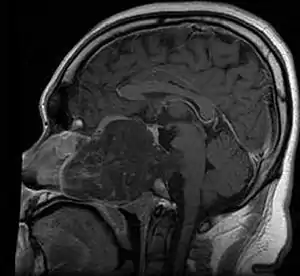

.jpg.webp)

Chordomas can arise from bone in the skull base and anywhere along the spine. The two most common locations are cranially at the clivus and in the sacrum at the bottom of the spine.[2]